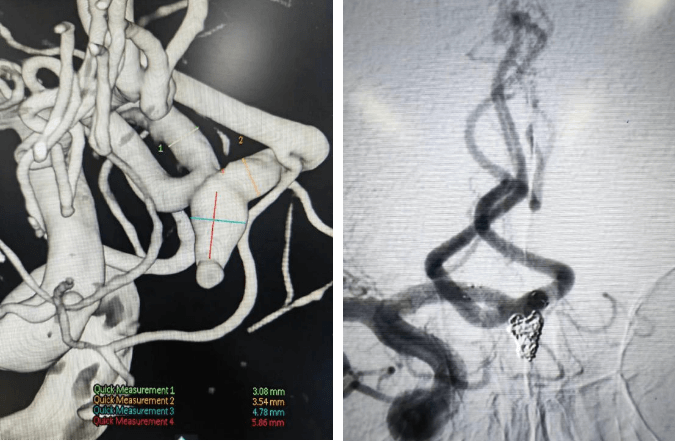

支架輔助動(dòng)脈瘤栓塞術(shù)前、術(shù)后對比

術(shù)前血管畸形及介入治療后血管畸形消失(治愈出院)